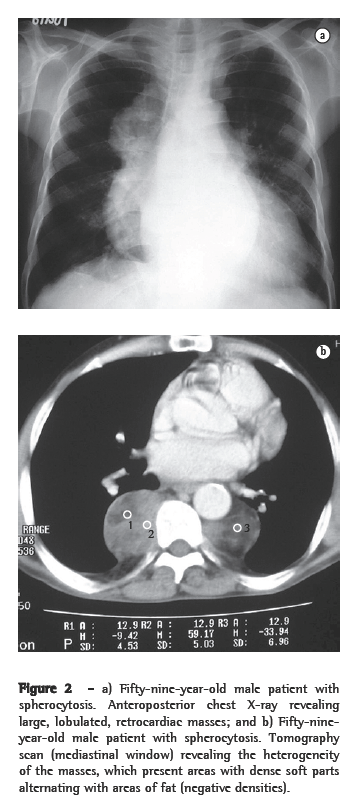

ResultsOf the six patients evaluated, four presented lower paravertebral masses. In three cases, the masses were bilateral and relatively symmetric, and, in one, the mass was unilateral (on the right). Regarding the content of the masses, the presence of adipose tissue was confirmed in three patients, and, in one of them, the quantity of adipose material was quite significant. In one patient, the masses were homogeneous, with dense soft parts (Figures 1a, 1b, 2a and 2b).

On CT scans, masses with dense soft parts, usually homogeneous, with characteristics similar to those described using conventional radiology,(1,2,5,6) and which might or might not be highlighted after administration of contrast material,(4,10) can be seen. This imaging method is important for analyzing the internal structure of the lesions, especially of those that are rich in fat,(5) in order to identify other paracostal masses, and for detecting bone alterations associated with certain hematologic diseases, such as thalassemia and sickle cell anemia.(6) In cases related to thalassemia, sickle cell anemia, or myeloid metaplasia, there can be widening of the medullary cavities of the ribs.(5) All of those aspects were identified in our cases. It is of note that two patients presented calcifications in the spleen, resulting from multiple infarcts, with autosplenectomy. Both of those patients had sickle cell anemia. This finding can also facilitate the differential diagnosis.

Active, recent lesions are richly vascularized, whereas old, inactive lesions have more adipose tissue and iron deposition. Between the two extremes, there are various combinations of findings, reflecting the different stages of evolution of the hematopoietic focus. Those histological differences are not represented on CT scans or MRIs. Recent, active lesions present dense soft parts on CT scans and intermediate signal intensity on MRIs (T1- and T2-weighted images). After administration of contrast material, there is usually some degree of impregnation in the active lesions. Old, inactive lesions can show increased density on CT scans, due to iron impregnation, or negative densities, due to adipose infiltration. On MRIs (T1- and T2-weighted images), old, inactive lesions can show high signal intensity, due to adipose infiltration, or low signal intensity, due to iron deposition.(4,8,12)